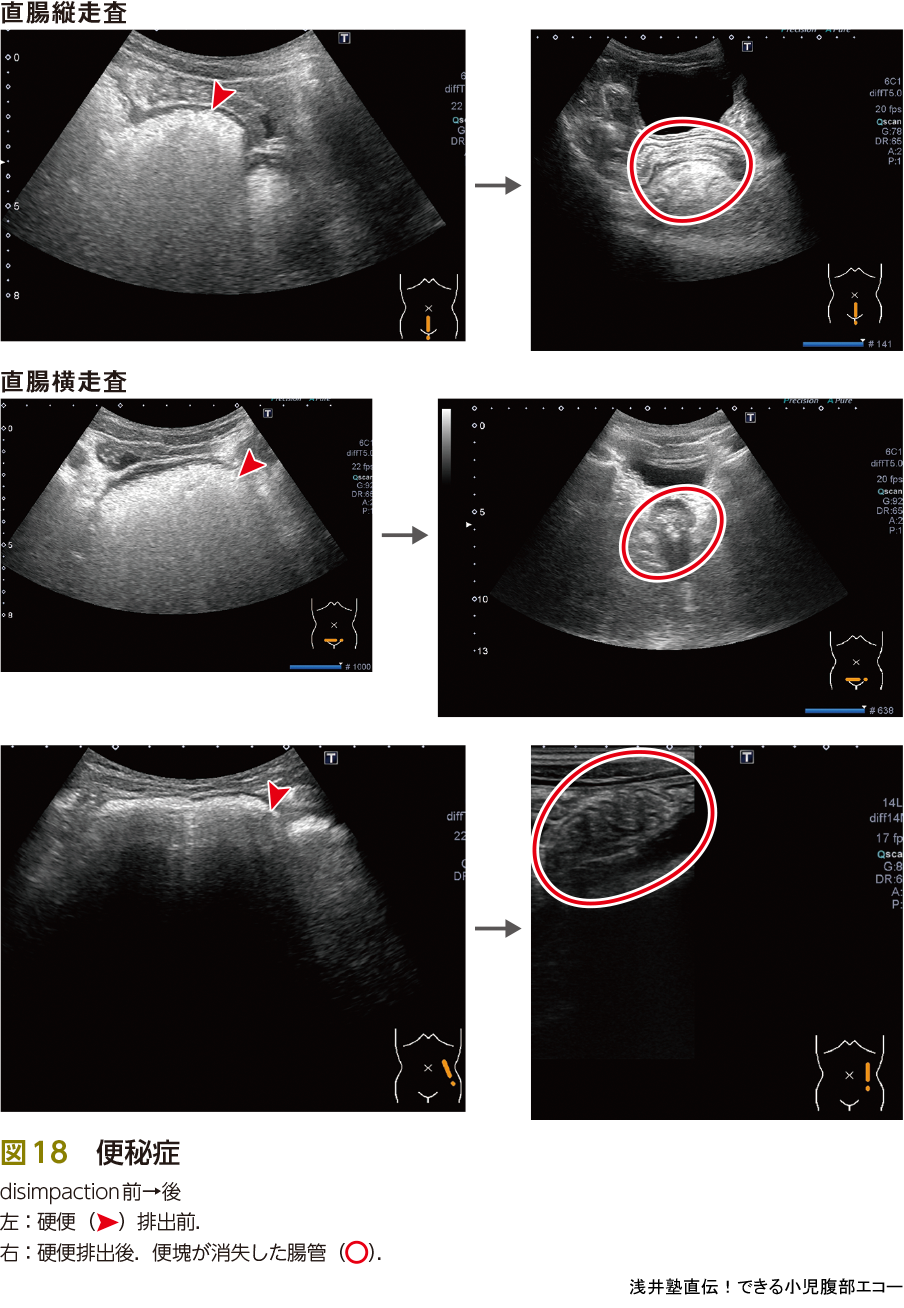

便秘は最も遭遇することが多い疾患の1つです(図17).たかが便秘,されど便秘です.下痢(や遺糞症)を主訴として受診する場合もあります(ピットフォール③参照).

腹部単純X線撮影で便の状況を観察し,便秘の診断をつけている現状かと思いますが,私はリアルタイム,被曝がなく,ベッドサイドでできるエコーが有用と考えます.エコースキルに自信がない場合や,ほかの疾患を想定するときは非常に有用な単純X線撮影ですが,便秘に関してはエコーファーストと考えています.「単純X線撮影1枚くらい」と,いわれることもあります.確かに,微々たるものであり大きな被曝の影響はないといわれています.

しかし,自分にとっては「そのくらい」であっても,相手はそう思っていないかもしれません.小児医療に携わるものとしては,少しでも無駄な被曝をなくしたい,放射線に対する無駄な不安を与えたくないという気持ちを根底にもつ必要があるのではないかと考えます.また浣腸などdisimpaction後の反応をみるためにも有用です(図18).

また,便秘症は病歴と触診が役に立ちます.自らの触診で便塊の貯留部位を推測し,エコーで確認(エコー輝度が高いほど硬い便),そして再度触診をして手に覚え込ませることで触診のスキルもアップします.